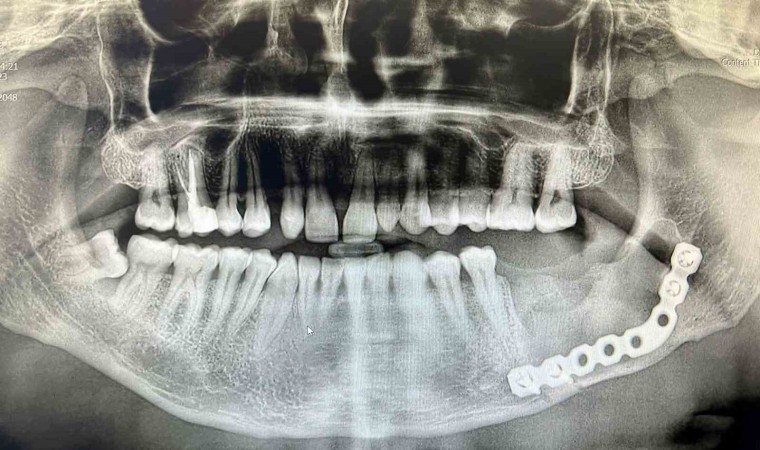

Sivas Ağız ve Diş Hastalıkları Hastanesinde benzerine az rastlanan bir ameliyat gerçekleştirildi. Çenesinde ileri derecede apse şikayetiyle hastaneye başvuran 43 yaşındaki hasta, uygulanan yöntemle sağlığına kavuştu. 37 numaralı dişi çekilen hastanın tomografi görüntüleri alındı. Hastanın 3D yazıcı sistemi ile çene modeli oluşturuldu. Oluşturulan 3D çene modeli üzerinde titanyum plak uyarlaması yapıldı. Uyarlamanın ardından Ağız, Diş ve Çene Cerrahisi Uzmanı Yunus Balel, genel anestezi altında hastayı ameliyat ederek, titanyum plak işlemini hastaya uyguladı.

“Bu uygulama, Sivas gibi genel anestezi ünitesi olan hastanelerde nadir yapılan işlemlerdendir. Bu kistler sınırsız büyüme potansiyeline sahiptir. Biz hastamızı geç evrede yakalamışız. 3D modelleme fikri benim aklıma geldi. Kullandığımız plak titanyum malzeme. Bu plağın bükümü ameliyat esnasında çok zor. Yaklaşık yarım saat süren bir durum. Bu da hastanın fazla süre entübe olmasına neden oluyor. 3 boyutlu bir model ürettik. Ağız dışında plağı uyumladık, ameliyat esnasında da 5 dakika uğraşarak uyumlamalara devam ettik. Bu model işimizi yarım saat ile 1 saat arası kolaylaştırdı.”

Sivas Ağız ve Dış Sağlığı Hastanesi Başhekimi Diş Hekimi Fuat Şen, bu uygulamanın Sivas’ta yapılmasının bölge için bir şans olduğunu dile getirerek, “Ameliyat yaklaşık 2 saat sürdü. Bu çok uygulanan bir ameliyat değil. Bu ameliyat ile hastamıza hem maddi hem de süre anlamında kolaylık sağlanmış oldu. Hastamız sağlığına kavuştu, kendisini taburcu ettik. Ağız ve Diş Sağlığı Hastanesi olarak uzman sayımızı artırarak bu tip işlemleri yapabilmek için çaba harcıyoruz. 2018 yılından bu yana genel anestezi altında zihinsel ve bedensel engelli hastalarımız ile çocuklarımızın da tedavilerini yapmaya başladık. Şu anda bölgemize hizmet veren bir hastaneyiz” dedi.